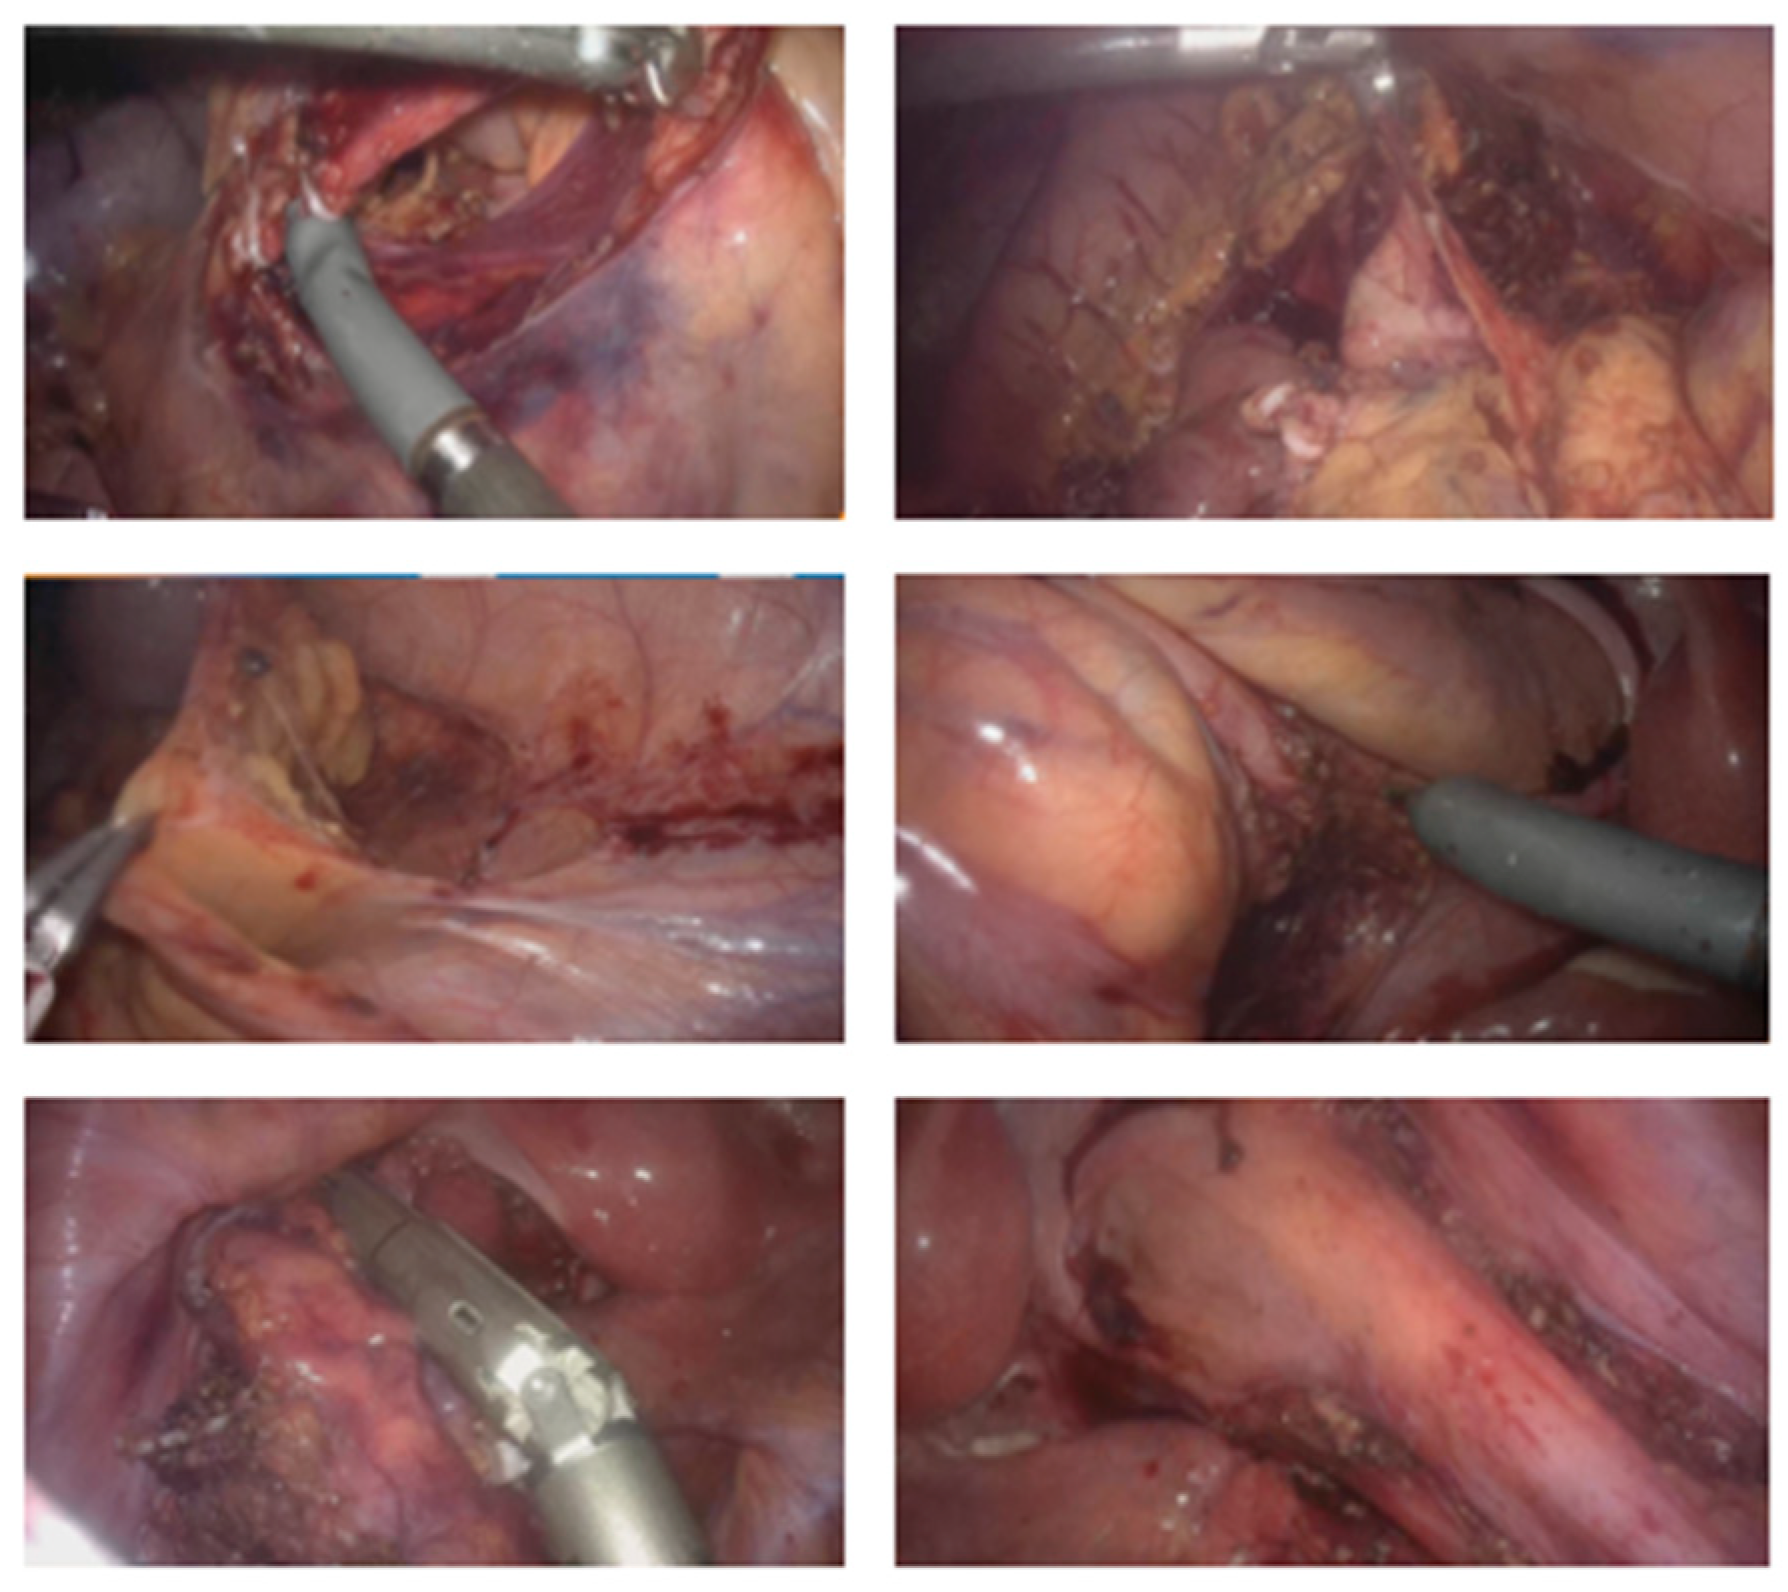

2.3.3. General Description of the Procedure

| Phase I Initial Steps and System Configuration | Docking Time: 3 min 25 s | - Operating table at 60 cm height; - Supine position in modified lithotomy; - 10° Trendelenburg; - 10° left lateral tilt. | Ports: - Four ports positioned diagonally from the left hypochondrium to the right iliac fossa; - Two robotic trocars of 8 mm; - Two robotic trocars of 11 mm (one for the camera, one for traditional laparoscopic instruments); - A 12 mm trocar for insufflation and assistance. System Configuration: - Arm 1 (8 mm): Tilt (+30°), dock, 45°—reserve; - Arm 2 (11 mm): Tilt (+30°), dock, 145°—endoscope/assistant port; - Arm 3 (8 mm): Tilt (−15°), dock, 225°—surgeon’s left hand (bipolar); - Arm 4 (11 mm): Tilt (−15°), dock, 315°—surgeon’s right hand (monopolar curved shears). | - Port placement; - System configuration and robotic arm docking. |

| Phase II Assisted Robotic Right Colectomy | N/A | Same as Phase I | As configured in Phase I | - Access to retroperitoneum between the superior mesenteric vein and ileocolic vessels; - Dissection and division of ileocolic vessels; - Identification and control of right colic and middle colic vessels; - Medial-to-lateral mobilization of the right colon; - Opening of the greater omentum to access the lesser sac and complete mobilization of the right colon. |

| Phase III System modification | Docking Time: 2 min 55 s | - 10–15° Trendelenburg; - 10–15° right lateral tilt. | System Configuration: - Arm 1 (8 mm): Tilt (−15°), dock, 45°—surgeon’s left hand (Cadiere grasper); - Arm 2 (8 mm): Tilt (−15°), dock, 145°—surgeon’s right hand (monopolar curved shears); - Arm 3 (11 mm): Tilt (+30°), dock, 225°—endoscope; - Arm 4 (11 mm): Tilt (+30°), dock, 315°—reserve (Cadiere bipolar forceps). | - Detachment of robotic arms; - Patient repositioning; - Redocking of robotic arms with a new configuration for left colectomy. |

| Phase IV Assisted Robotic Left Colectomy | N/A | Same as Phase III | As configured in Phase III | - Division of inferior mesenteric artery and vein; - Medial-to-lateral dissection of the left mesocolon; - Opening of the left paracolic gutter up to the splenic flexure; - Mobilization of the splenic flexure; - Disconnection of the greater omentum from the left transverse colon; - Complete mobilization of the transverse colon; - Partial mesorectal dissection and division of the rectum below the rectosigmoid junction. |

| Phase V Laparoscopic Assisted Phase | N/A | - Suprapubic (Pfannenstiel) incision | - Removal of robotic trocars; - Use of traditional laparoscopic instruments. | - Incision for extraction of surgical specimen; - Division of the ileum and introduction of a 28 mm EEA circular stapler anvil; - Transanal ileorectal anastomosis; - Integrity test of the anastomosis with methylene blue; - Closure of the ports. |